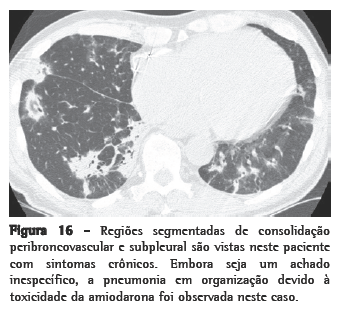

Padrão 3. Opacidade pulmonar aumentada

Opacidade pulmonar aumentada pode ser descrita como opacidade em vidro fosco ou consolidação. A opacidade em vidro fosco (Figura 15) é uma opacidade pulmonar aumentada que não obscurece os vasos associados e representa anormalidades abaixo da resolução da TCAR. A consolidação (Figura 16) é uma opacidade pulmonar aumentada na qual os vasos são obscurecidos e representa uma doença confluente. Estes achados são muito inespecíficos e podem refletir doenças que são primariamente alveolares, intersticiais ou mistas. O diagnóstico diferencial entre opacidade em vidro fosco e consolidação muitas vezes é sobreposto e é predominantemente baseado pela duração dos sintomas: agudo ou crônico (Quadro 8). A distribuição dos achados (focal, segmentado ou difuso/simétrico) pode ser útil no estreitamento do diagnóstico diferencial (Quadro 9).

Formas crônicas de pneumonia em organização

Formas indolentes (smoldering) e crônicas de PO não-infecciosa podem produzir achados clínicos de dispnéia progressiva, febre baixa, sintomas constitucionais e consolidações pulmonares que não respondem ao tratamento padrão para pneumonia infecciosa. Muitas condições podem resultar em PO. Em um estudo conduzido na cidade de São Paulo, Brasil, envolvendo 95 pacientes, a PO era idiopática em um terço dos casos e secundária a uma causa identificável nos casos remanescentes.(90) As causas mais comuns eram: drogas (especialmente amiodarona e MTX), exposição ambiental (tal como as observadas em PH), aspiração crônica e DTC. Consolidações, centrais ou periféricas, foram encontradas em 64% dos casos; opacidade em vidro fosco, em 53%; e nódulos, em 26%. A biópsia transbrônquica foi diagnóstica em 58% dos casos.

Na pneumonia em organização criptogênica (POC), padrões típicos na TC consistem em consolidações parenquimatosas periféricas com broncogramas aéreos e opacidades em vidro fosco com associação variada.